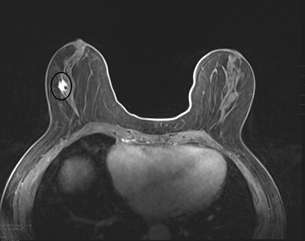

Case: Invasive Lobular Carcinoma Figure 4

Screening DBT on a 75-year-old female revealed an asymmetry in the central region of the right breast at posterior depth located 10 centimeters from the nipple. There is a probable correlate on medial breast on CC view.